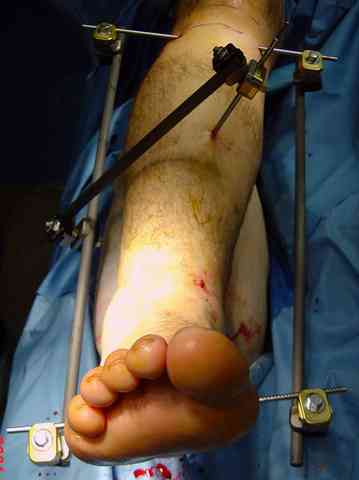

Яков изложил все необходимые аспекты лечения переломов пилона, и, не желая менять тему, решил выставить нашу точку зрения в двух клинических примерах.

При лечении внутрисуставных переломов типа "Pilon"

или "Tibial Plateau" на голени, применение простых

наружных фиксаторов типа "Spanning ExFix" или "Travelling ExFix" стал одним из стандартом этапного лечения.

В первые часы после поступления больным экстренно накладывается простой фиксатор из двух поперечно проведенных стержней или сооружается "Delta

Frame" в зависимости от места локализации, и проводится дистракция.

Здесь выставлена пара случаев перелома пилона, оба

случая леченные этапным наружным фиксатором.